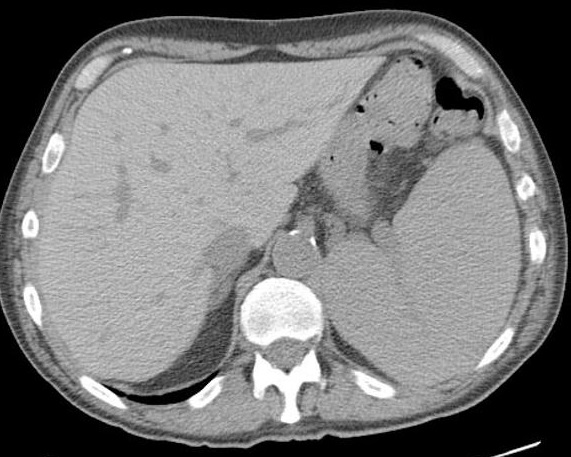

Image radiologique TDM en coupe coronal

d'une splenomegalie . La rate est tres volumineuse

compress angle colique gauche et le rein gauche à

inferieuse , La coupole diapragmatique est

legerement pousse en haute . On peut en s'observe

image de plaque de infartus parenchymateuse

hypodense à bord inferieuse de la rate |